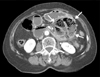

A 74-year-old woman presented to the Emergency Department with persistant right upper quadrant pain that began 3 hours prior to presentation. She had an unremarkable medical history, but asymptomatic gallstones were detected during routine check-up. More specifically, she had no history of abdominal surgery or abdominal pain prior to this visit. Physical examination revealed a thin woman (height, 156 cm; weight, 49 kg) with a blood pressure of 110/70 mmHg, a pulse of 64 beats/min, and a body temperature of 36.6℃. The abdomen was tender in the right upper quadrant. No guarding and rebound tenderness were noted. The laboratory data showed neutrophilia (white blood cells, 9,710 / mm3 with 81.4% segmented neutrophils). Other blood chemistry parameters including liver function test were unremarkable. CT revealed multiple gallstones with gallbladder wall thickening, marked dilatation of stomach and duodenum and a sac-like mass of small bowel loops to the left of the ligament of Treitz (Fig. 1) suggesting acute cholecystitis and left paraduodenal hernia. After performing CT, the patient developed bilous vomiting without left abdominal pain. We proceeded to perform laparoscopic exploration of the abdomen with cholecystectomy. The defect was located at the Treitz ligament where proximal jejunal loops were noted to be herniating through the defect (Fig. 2). About 50 cm of jejunal loops were easily reduced and the bowel appeared viable. The 3-cm defect was closed using 3-0 Vicryl intracorporeal interrupted sutures. Laparoscopic cholecystectomy was then performed. The total operation time was 105 minutes. The postoperative course was uneventful and the patient was discharged on postoperative day 4. During the 6 months follow-up period, the patient remained completely free of symptoms.